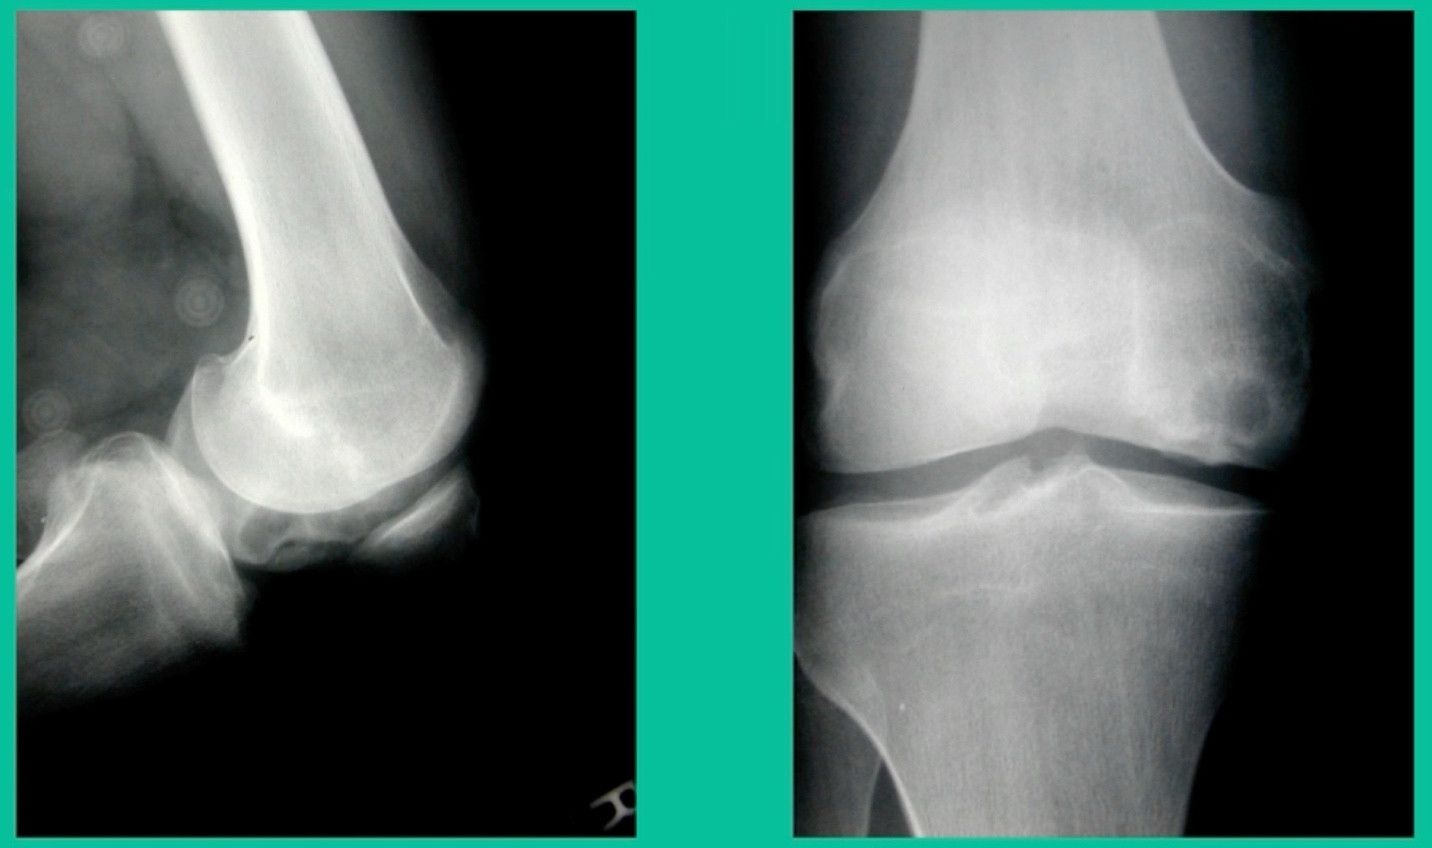

43-Year-Old, symptomatic medial femoral condyle.

D1 football player formally, affecting ADLs. For this one, I initially just wanted to watch it. This looks pretty small when he came in. Let’s see what happens. Six months later, this is where he progressed to.

We get in there, it’s delaminated, not much bone, nothing to fix in my mind, and so we drilled it.

How do these do? There’s actually reasonable data for marrow stimulation for OCD. But if you have the option for small defects, I would prefer an osteochondral allograft over microfracture based on the literature. That’s the take-home. Marrow stimulation, if you do it, you’re probably better off drilling it. We showed that we could reduce revision rates with marrow stimulation by two-thirds if you drill it versus use a microfracture awl.